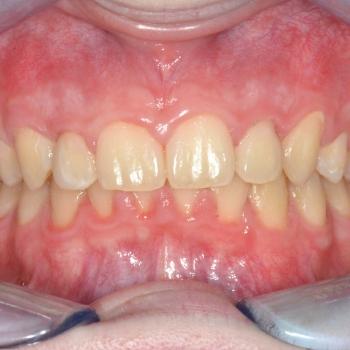

Balázs és édesanyja konzultáció céljából keresett fel, hogy egyértelműen kiderüljön számukra szükséges-e a fogszabályozó kezelés vagy sem. Már rögtön az első vizsgálat alkalmával fény derült több olyan problémára is, melyek fogszabályozást igényelnek. Ilyen volt például a súlyos mélyharapás, a hátrafelé dőlő felső metszők, illetve az Angle II. osztályú harapási eltérés is. A mintavétel, a röntgenek és a fotók kiértékelése után további problémaként merült fel a felső fogív szűkülete és a kismetszők méretaránytalansága, azaz a túlzott keskenységük.

A kezelést Quadhelix fogszabályozóval kezdtük el a felső fogív tágítása érdekében. Ezután került felragasztásra az alsó és felső fogívre a Balázs és szülei által kiválasztott fém önligírozó fogszabályozó. Ezen túlmenően Bite turbo harapásemelő segített a mélyharapás, intermaxillaris gumihúzás pedig az Angle II. osztályú harapási eltérés korrigálásában. A fogak méretaránytalansága miatt a kezelés végén a kismetszőket tömőanyaggal építettük fel, hogy a tökéletes harapáshoz résmentes fogazat társuljon. A fogak felépítéséhez az adott fogakat nem kell megfúrni, a tömőanyag kizárólag ragasztásos módszerrel rögzül, így nem károsodik a fogzománc.